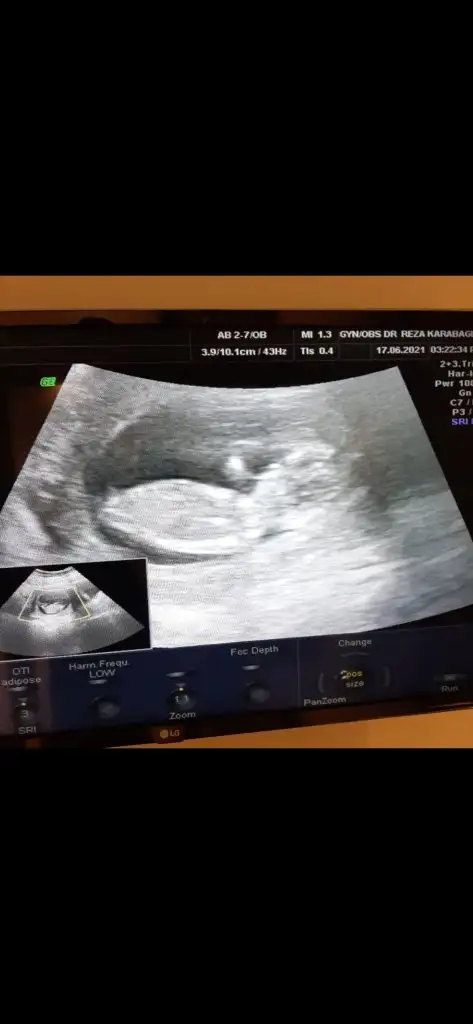

Yukardaki pipi mi ışık yansıması mı ben de çözemedim başta bariz kız yazdım ama sonra eğer ışık yansıması falan değilse pipi olabilir diye de düşünmedim değil

Ama çok fazla açı var onda nubta 30 derece açı olur en fazla. Nevossss

Selammm ben de kontrolden çıktım. 11+6. İkili test yaptırdım usgde sıkıntı yok cinsiyete de kız dedi çok mutlu oldum bir oğlum var. Baya emin konuştu.. 1 aya belli olur iyice

9+2 karından bakıldı. TtulperdeBirumuttur yasamak